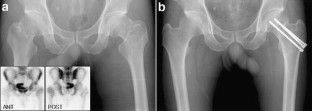

Fig. 1